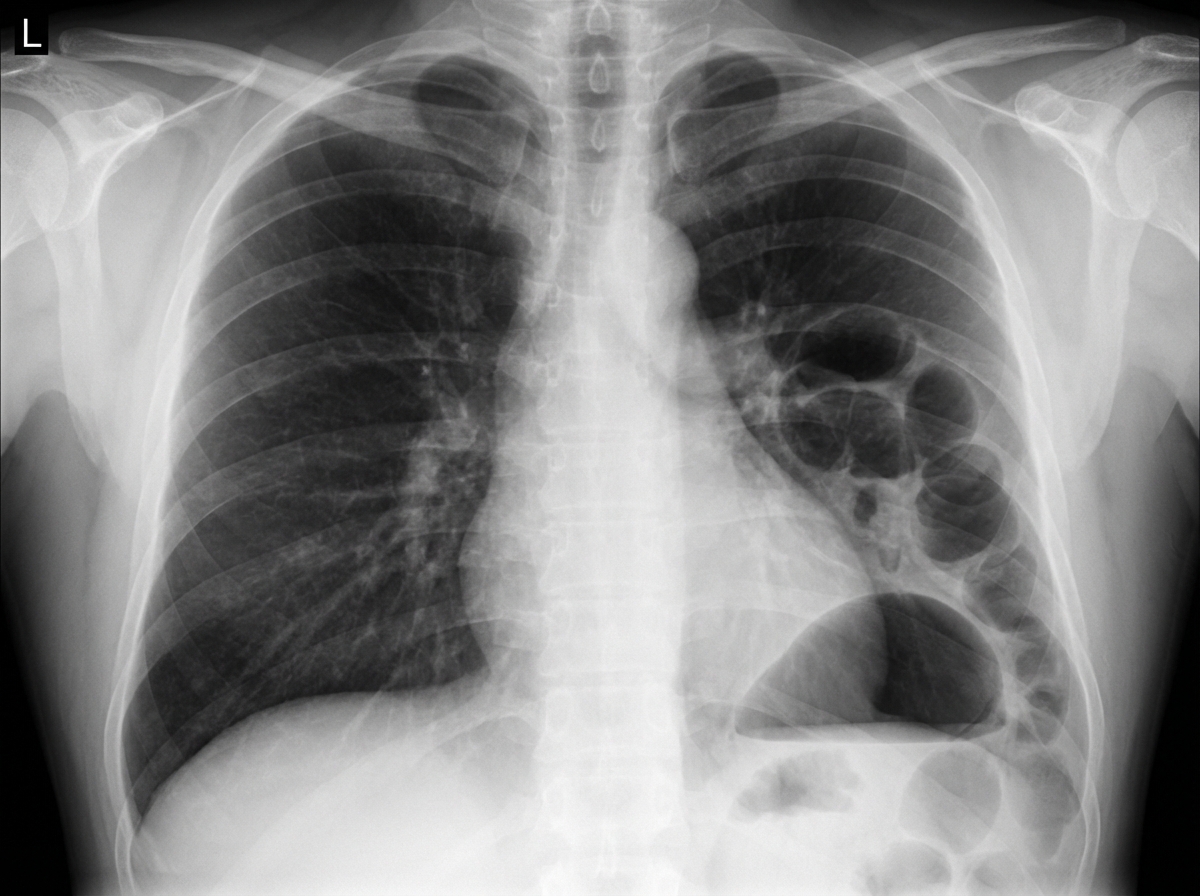

- ⚠️ Red Flags: Severe cardiopulmonary disease (e.g., EF < 30%, severe COPD), recent MI, significant hypovolemia.